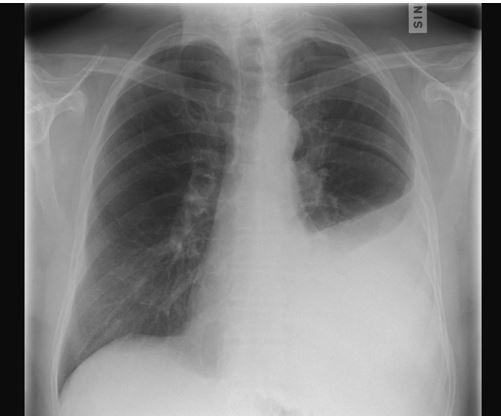

Toimenpide on turvallinen, eikä siitä aiheudu säteilyaltistusta. Toimenpiteen jälkeen otetaan tarvittaessa kontrollikeuhkokuva. Erittäin harvoin toimenpiteen komplikaationa kehittyy ilmarinta tai verenvuoto.